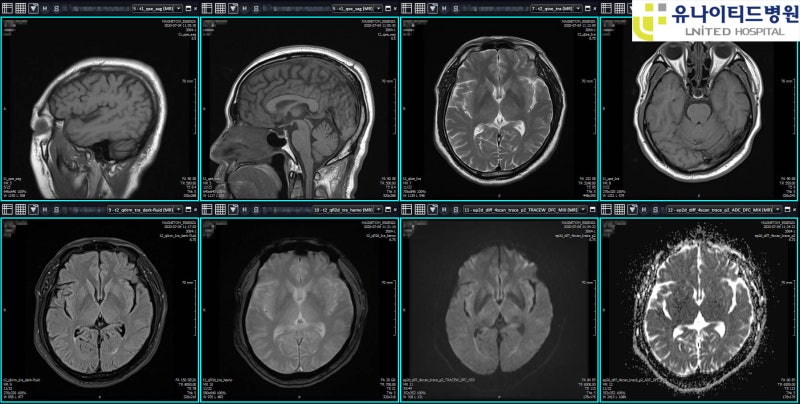

이런 두통이나 어지럼증으로 병원 진료를 생각하고 있다면 뇌·뇌질환 MRI 촬영을 생각하고 있다면 이 내용을 기억하시기 바랍니다.2023년 10월부터 뇌·뇌질환 MRI에 적용되는 건강보험이 변경됩니다!

두통과 어지럼증은 매우 자주 발생하는 증상인 만큼 건강보험 적용이 강화되고 진료의사의 의학적 판단에 따라 뇌질환이 의심되는 경우에만 MRI 검사에 건강보험이 적용됩니다.

앞으로는 단순편두통, 만성두통 등 진료의가 의학적으로 MRI 검사의 필요성이 낮다고 판단한 경우에 환자의 선택으로 MRI 검사를 하게 되면 건강보험 적용이 불가능해집니다.다만 기존 뇌질환이 확진되거나 신경학적 검사 등에서 이상이 있는 경우에는 기존과 같이 건강보험이 적용된다는 점을 참고하시기 바랍니다.